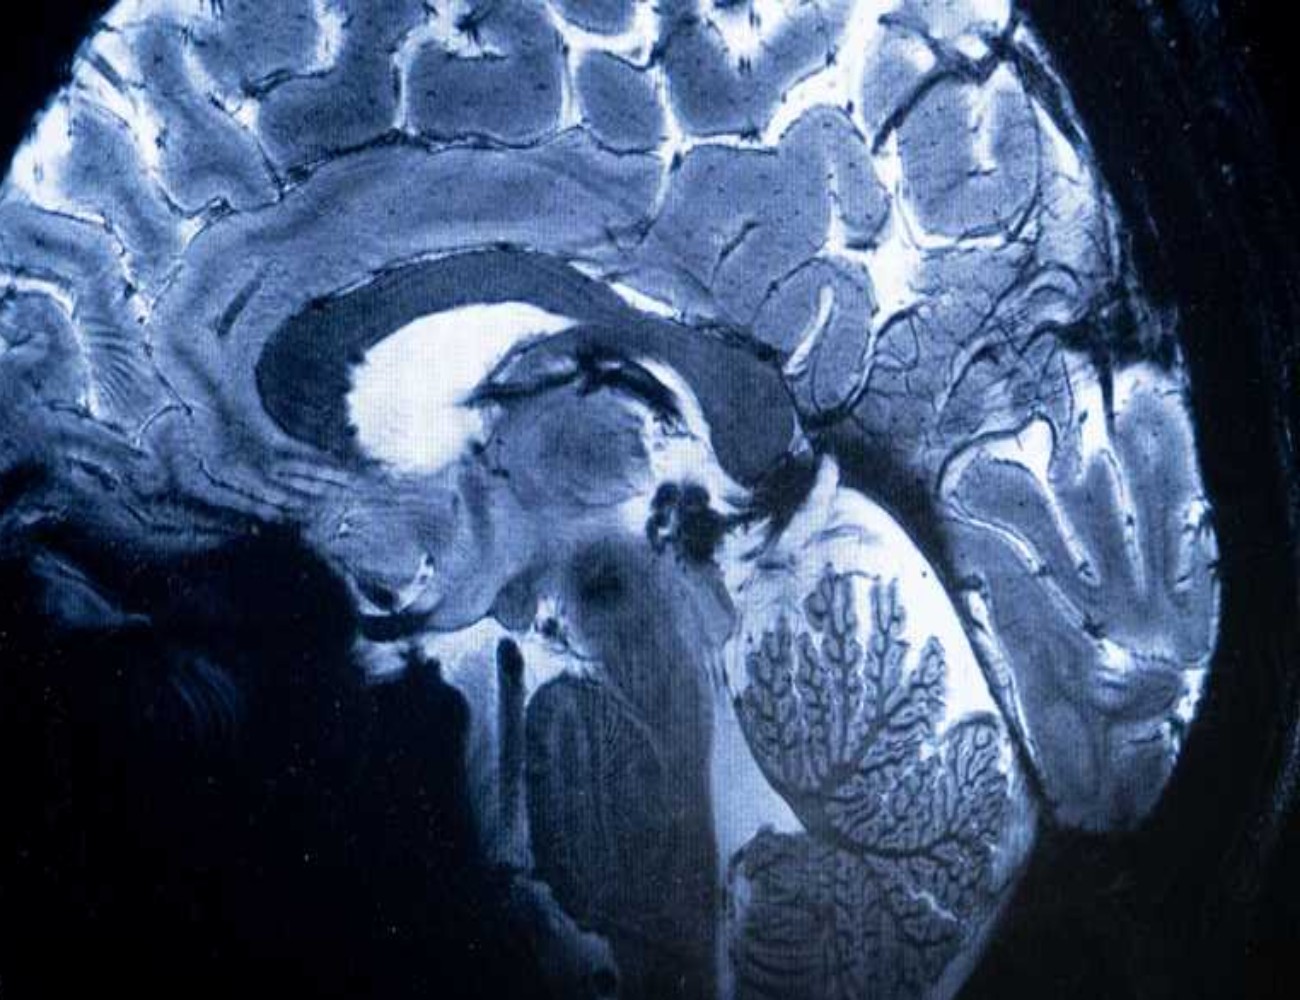

وأظهرت عمليات مسح التصوير بالرنين المغناطيسي لـ30 مريضا أدخلوا المستشفى بسبب "كوفيد 19" في وقت مبكر من الوباء قبل نشر اللقاحات، علامات على التهاب في جذع الدماغ، وهو جزء صغير لكنه بالغ الأهمية لأنه يتحكم بوظائف الجسم التي تدعم الحياة، مثل التنفس والنبض وحركة الدم، وتشير عمليات المسح إلى أن الإصابات الشديدة بفيروس كورونا يمكن أن تثير رد فعل مناعيا يؤدي إلى التهاب جذع الدماغ، مما يسبب أعراضا يمكن أن تستمر لأشهر بعد خروج المرضى من المستشفى، وذلك حسب الدراسة المنشورة في صحيفة "برين" العلمية.

واستخدمت روا وزملاؤها أجهزة تصوير بالرنين المغناطيسي قوية لفحص أدمغة المرضى، وكشفت هذه الأجهزة عن تفاصيل كافية لرؤية الالتهابات والتشوهات الدقيقة في أنسجة جذع الدماغ، علما أن جميع المرضى أدخلوا إلى المستشفى بسبب إصابات شديدة بفيروس كورونا قرب بداية الوباء.

وسلطت الفحوصات الضوء على التشوهات المرتبطة بالالتهاب في أجزاء متعددة من جذع الدماغ، التي ظهرت بعد أسابيع من دخول المرضى إلى المستشفى، وكان الضرر لا يزال واضحا في عمليات المسح بعد أكثر من 6 أشهر.